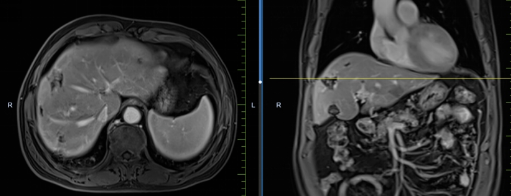

患者馬某某,男,60歲,因腹部不適行胃鏡及腹部CT,提示胃癌、多發(fā)淋巴結(jié)轉(zhuǎn)移、肝轉(zhuǎn)移,胃部病灶大小約11*6cm,淋巴結(jié)最大病灶約6*3cm,肝臟病灶最大約8.8*7cm。經(jīng)6周期化療+免疫,聯(lián)合中醫(yī)中藥后,病灶明顯縮小,進(jìn)入維持治療階段,身體狀況與常人無異。

治療后